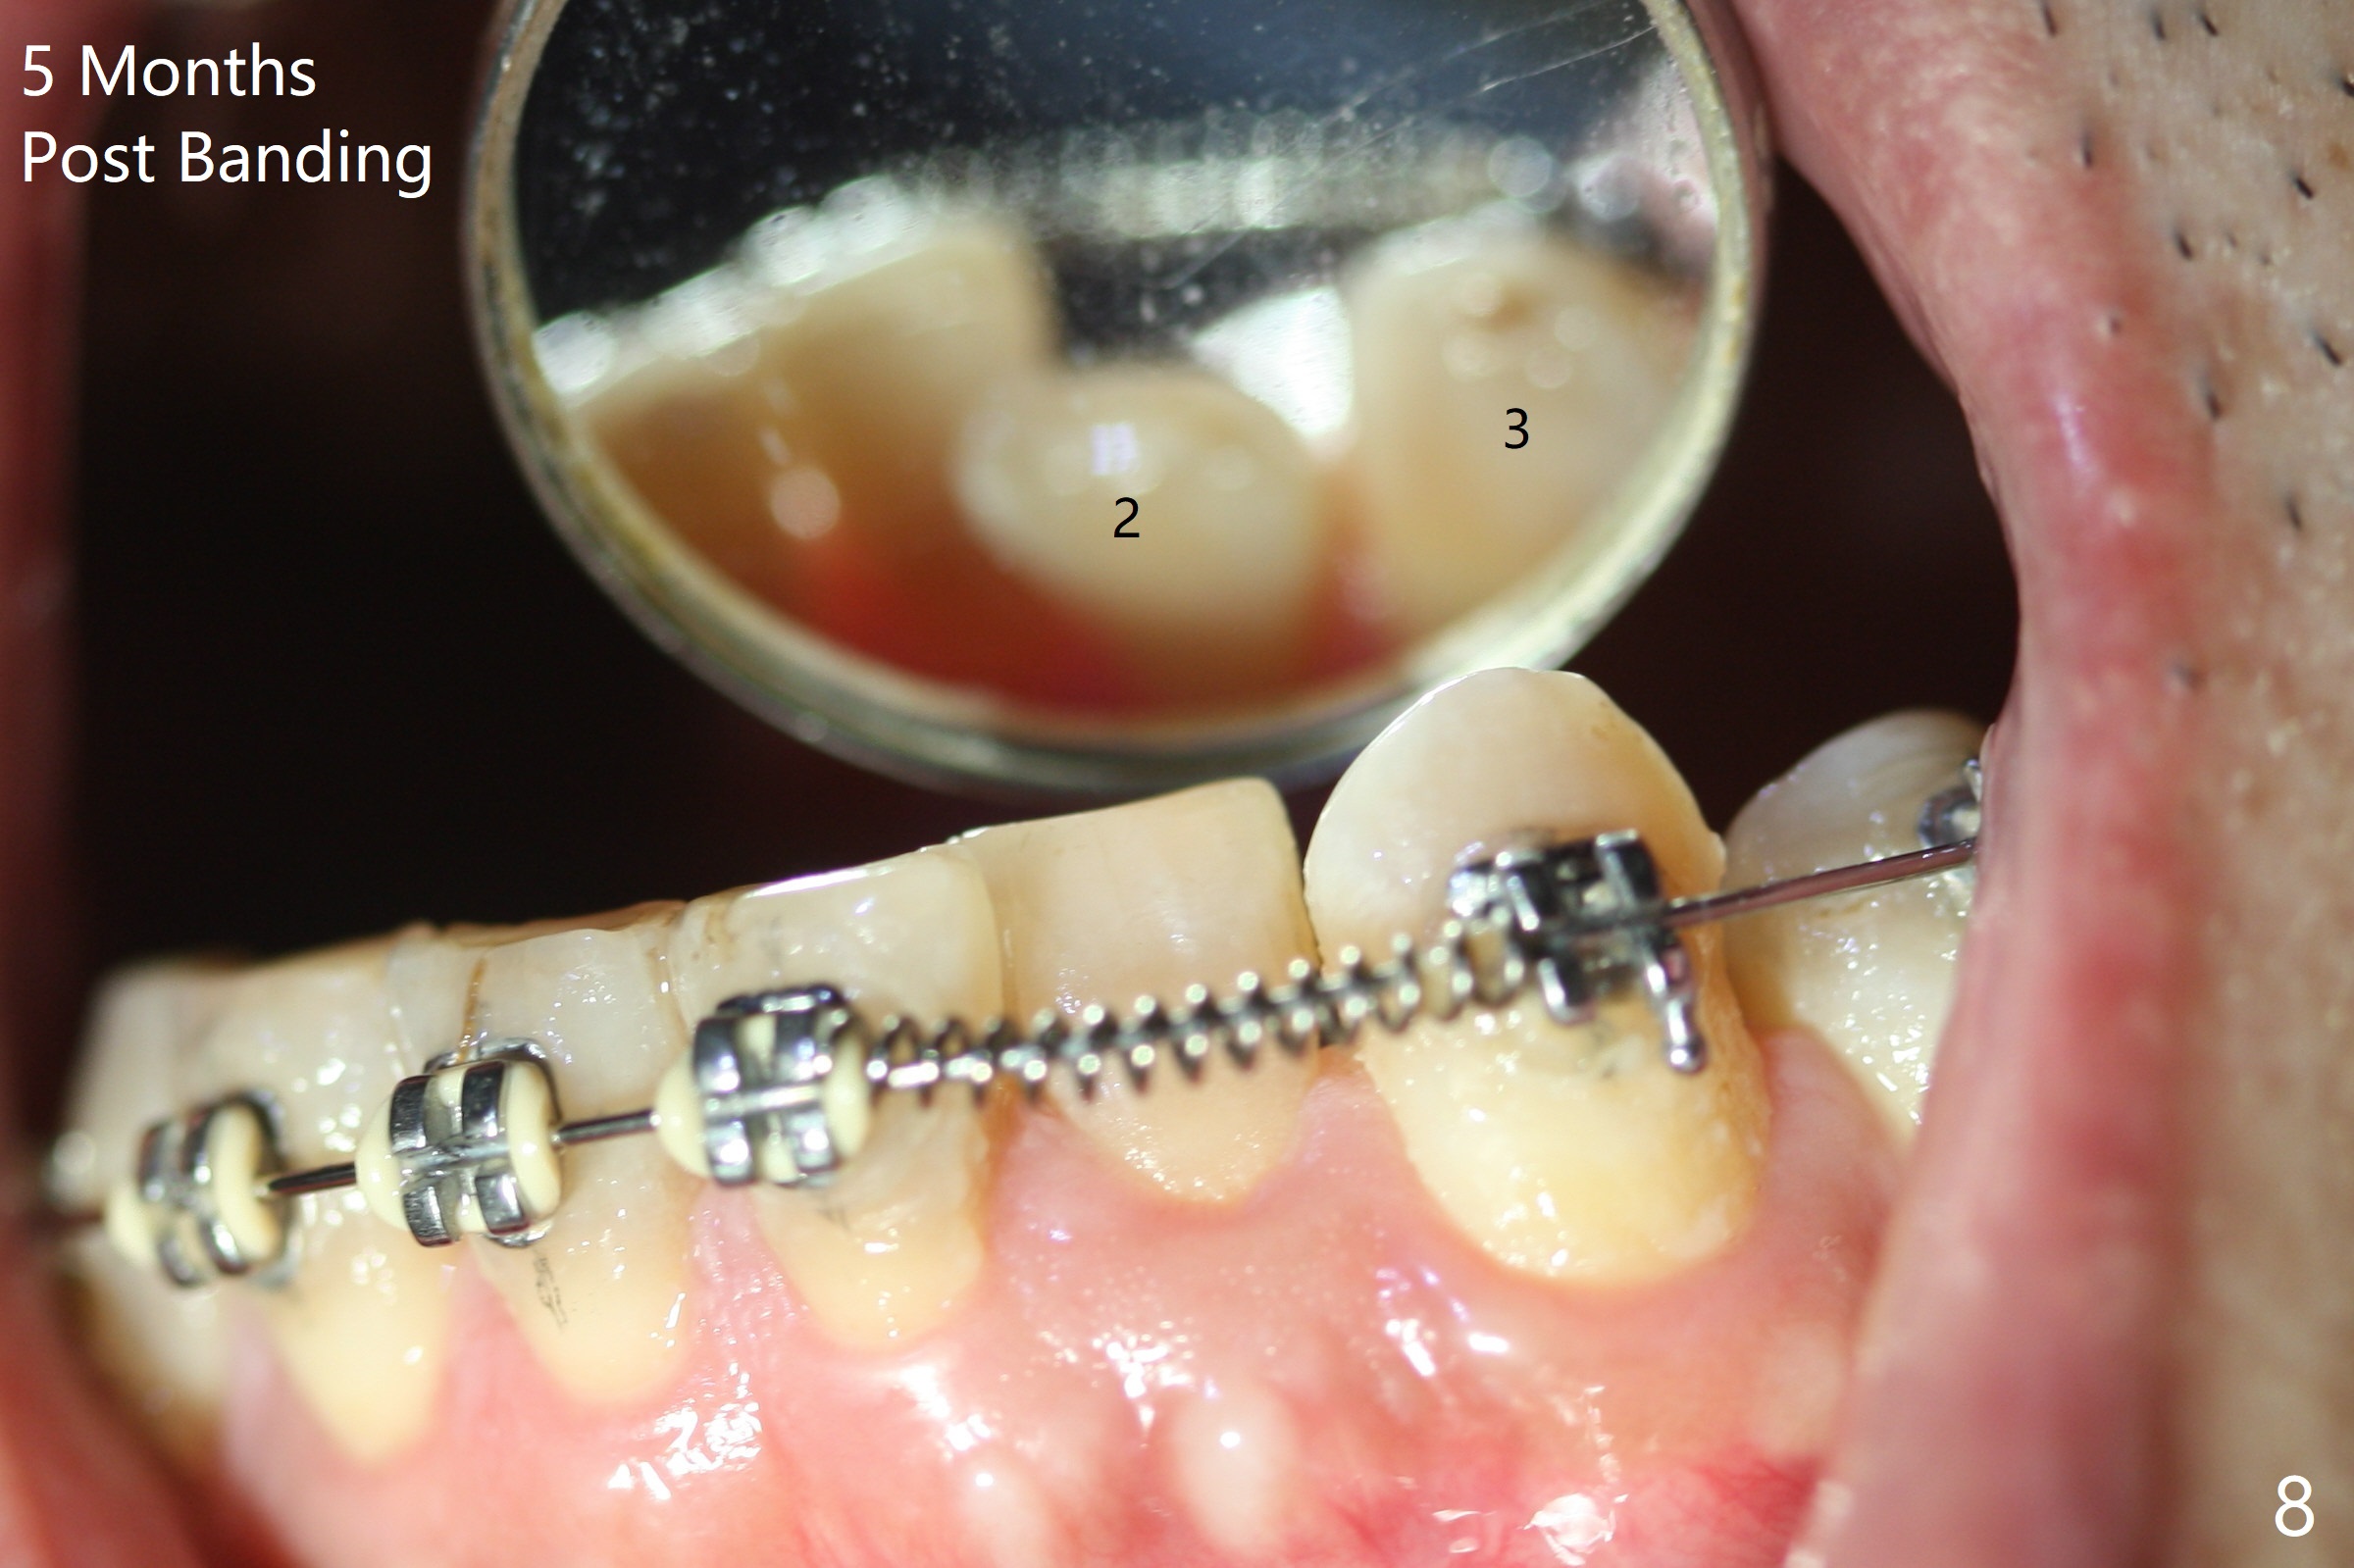

Two weeks post provisionalization over implants at #18 and 19 (4.5 months postop), acrylic is added to the provisional (Fig.1 *) and composite is placed on the other side (Fig.2 *) for clearance (Fig.3). Six days post bracketing, the diastema between LL5 and 6 decreases (Fig.4 between arrows, as compared to Fig.3), suggesting uprighting and distalization of the affected tooth. The diastema increases by trimming the mesial surface of LL6 provisional (Fig.5 *) prior to power chain placement. More acrylic is added to the occlusal surface of LL 6 and 7; more composite to that of UR3 (as compared to Fig.2) for clearance. Power chains change every week. LL5 is uprighted and distalized 1.5 months post banding (Fig.6,7 (14 niti)). Anterior brackets will be placed to correct LL2 cross bite next visit. Three weeks post open coil spring (5 months post initial banding), there is a space between LL2 and 3 (Fig.8) and between LL3/4 (Fig.9). The latter reduces instantly post power chain between LL3 and 6 (Fig.10). There is enough space for LL2 and sling shot is used to correct the cross bite 6.5 months post initial banding (Fig.11). The cross bite is corrected in 1.5 months after occlusal clearance is established (Fig.12). The lower left alignment is within normal limit, although in cross bite with the opposing dentition, immediate post molar crown cementation (Fig.13).